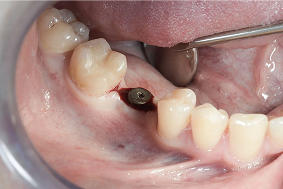

Natychmiastowe obciążenie

Protokół rehabilitacji protetycznej na implantach, polegający na tym, że pacjent opuszcza gabinet stomatologiczny w dniu zabiegu implantacji z tymczasową w pełni funkcjonalną protezą przykręconą do wprowadzonych wszczepów.

- W zależności od warunków kostnych u pacjenta oraz technicznego planu implantacji możliwe jest natychmiastowe osadzenie korony protetycznej na implancie zaraz po jego wszczepieniu. Taka sytuacja kliniczna określana jest jako natychmiastowe obciążenie implantu.

PORÓWNANIE: NATYCHMIASTOWE OBCIĄŻENIE A KLASYCZNY PROTOKÓŁ